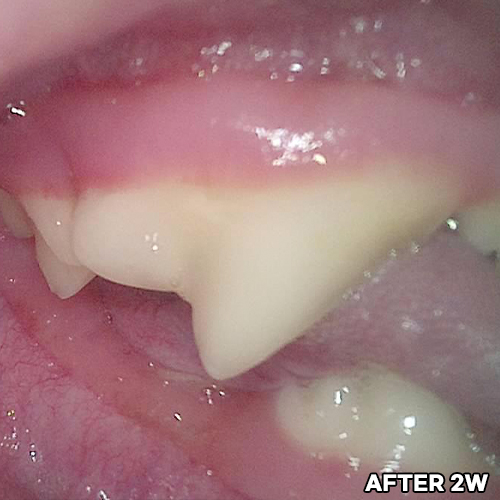

[강아지 치아의 구멍 레진치료 후 2주 경과]